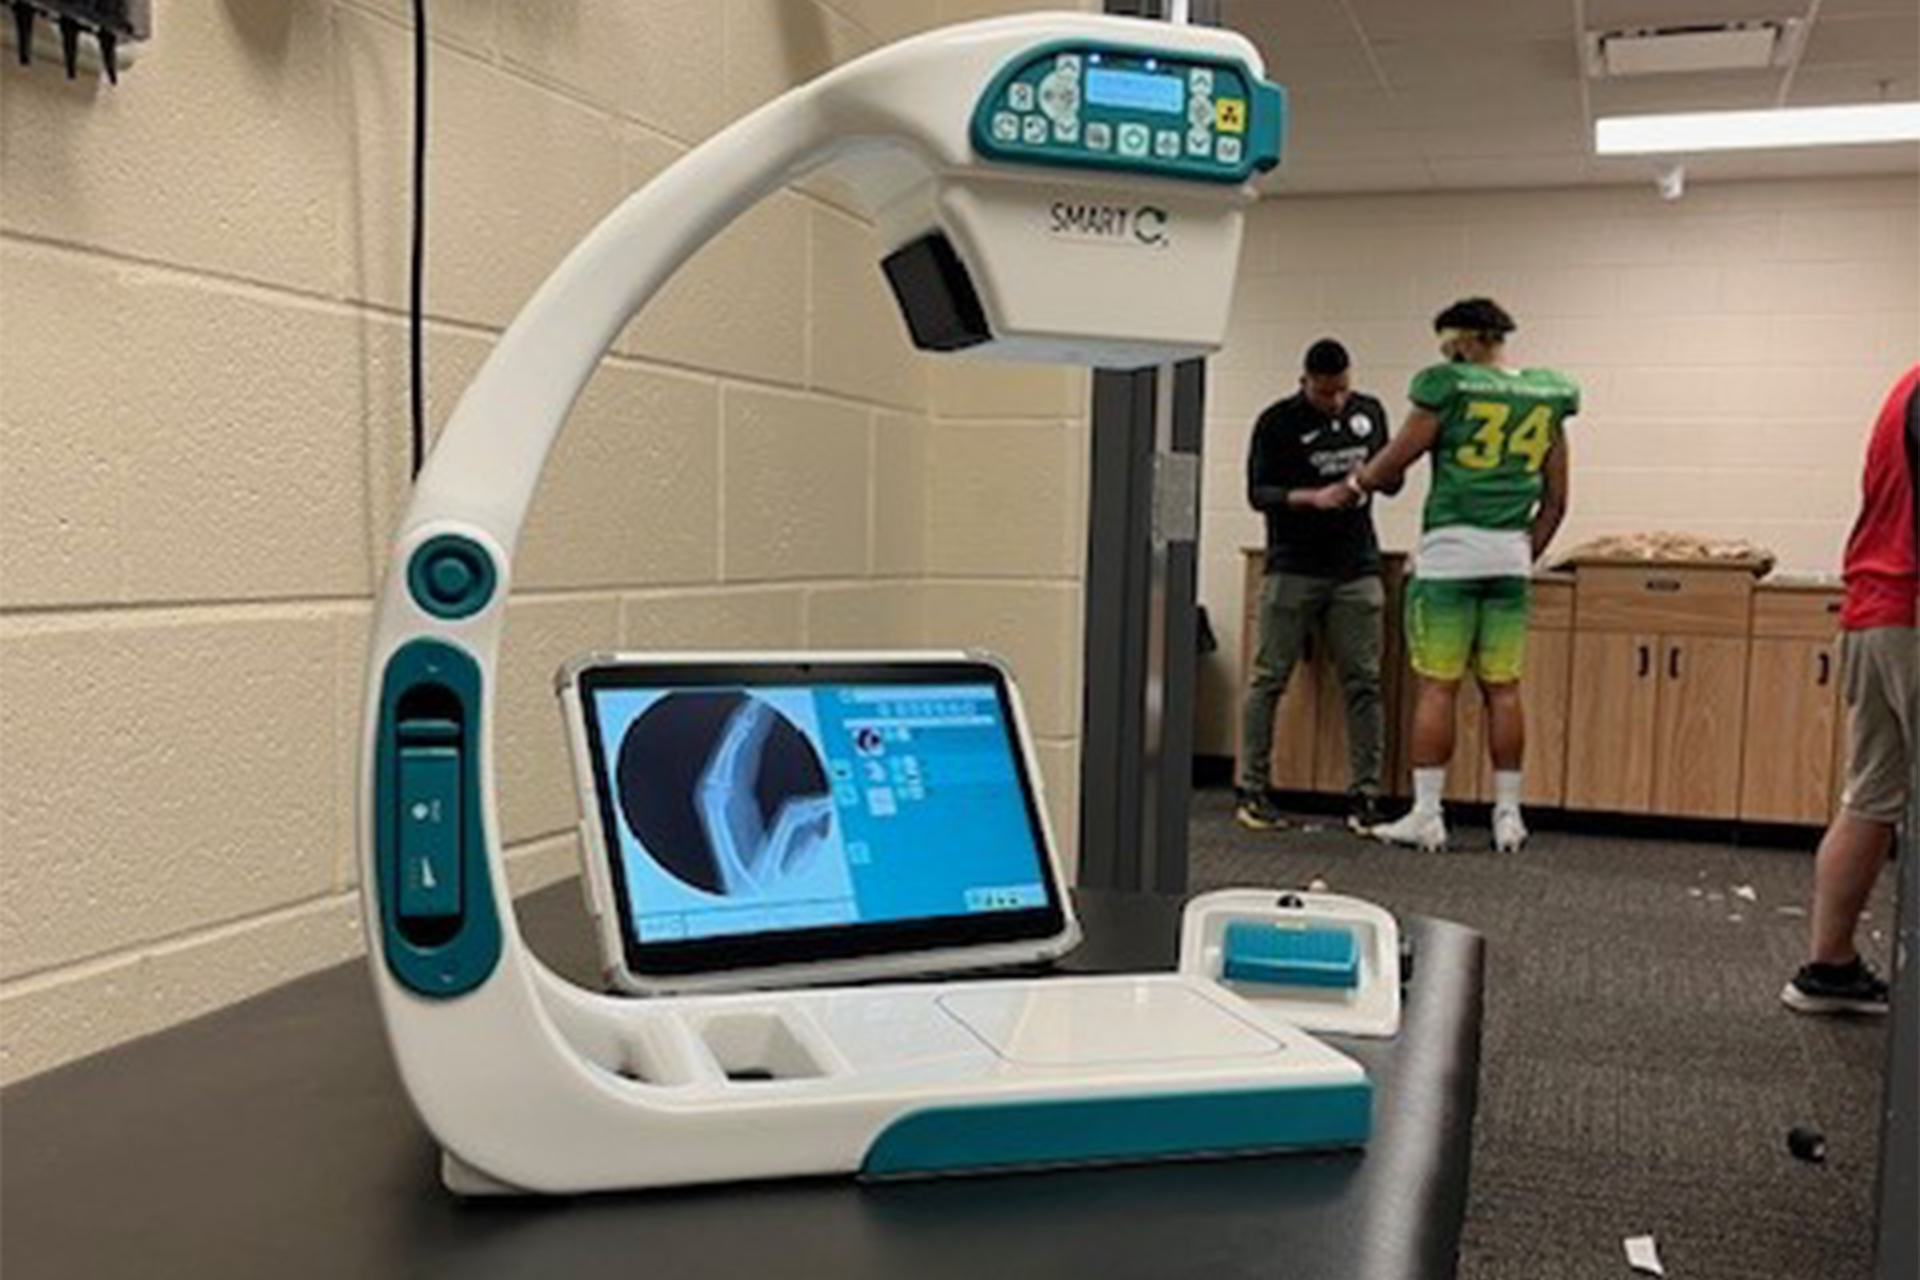

Although having a SMART-C® in your trainer’s room or dugout has helped professional & collegiate teams make more informed return to play decisions at the point-of-care, another use-case has emerged that greatly expands the utility of your SMART-C®: from an x-ray system used solely during injury diagnosis, to a device used during player recruitment, with the ability to transport and use the SMART-C® in your development league overseas.

Why SMART-C® is the ideal x-ray system for the development league?

SMART-C® is a 16 lb. mini c-arm that can be checked-in as luggage by training staff: SMART-C® and all accessories available in a pelican case with a total weight is under 50 lbs. SMART-C® is a Swiss army knife that can be used during the season to aid in injury diagnosis, and in the offseason, during player recruitment

100% battery operated: Enabling medical staff to take x-rays in any location, regardless of their access to stable AC-line power.

State of the art detector & software: SMART-C® contains a highly sensitive detector and advanced image processing algorithms that enables medical professionals to view and assess growth plate development with high quality x-ray images, in order to determine an athlete’s biological age.